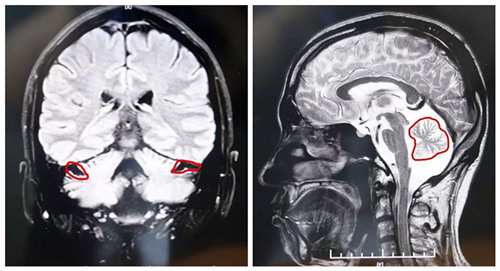

▲MRI显示,患者小脑萎缩状况明显